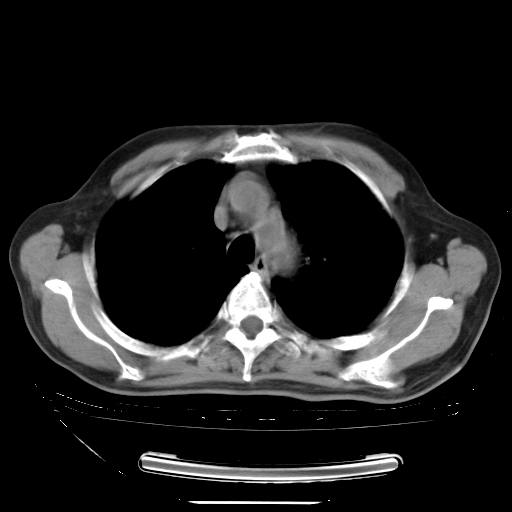

今天复查肺部CT,发现双肺广泛磨玻璃样改变。所以我把3月19日和5月9日相隔50天的肺部CT上传。请大家会诊。

2009年3月19日肺部CT片。

2009年3月19日肺部CT

大致读了系列胸部CT:纵隔窗无明显异常,肺窗:从4、27至今:主要是双肺中下野外带可见毛玻璃样改变,目前处于急性肺泡炎阶段,至于原因考虑1、结替组织或胶原血管性疾病所致?2、恶性疾病如恶组在肺部所致的表现或细支气管肺泡癌?3、药物或其它原因如肺蛋白沉着症所致肺泡炎目前不太可能?总之,明天就去请我院的呼吸科、感染科、血液科和临免专家会诊哈。